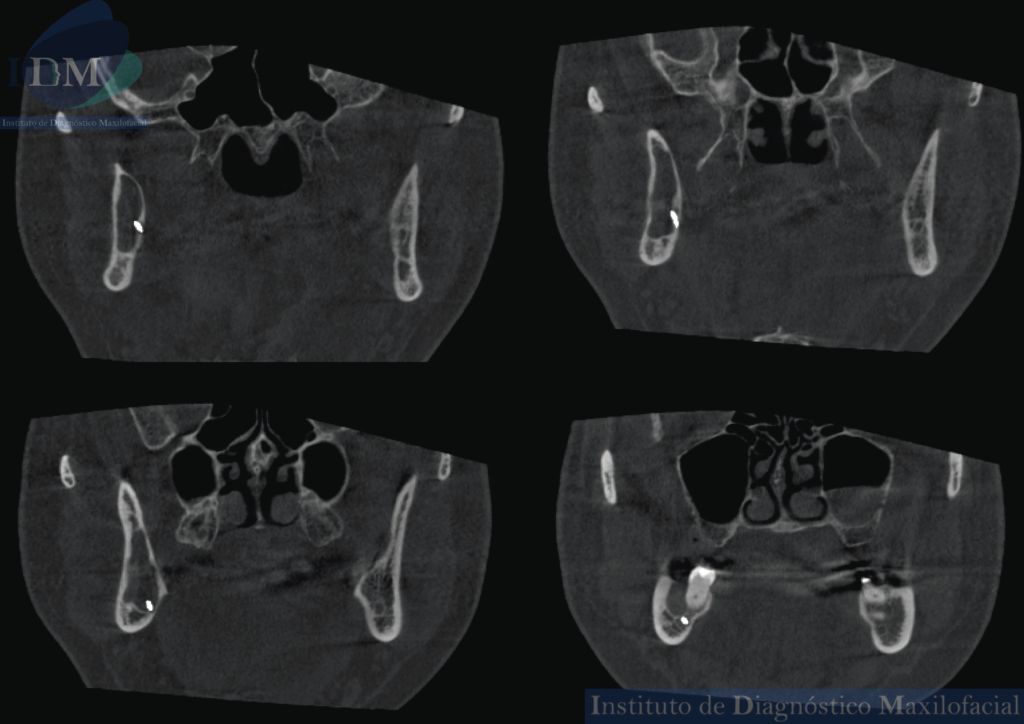

A la evaluación de la tomografía computarizada en los cortes axiales, coronales y tangenciales se aprecia una imagen hipodensa de aproximadamente 38 mm x 16, 65mm x 5.98 mm que se extiende en sentido anteroposterior desde la raíz distal de la pieza 47 hasta la escotadura sigmoidea de la rama mandibular, además presenta un patrón de crecimiento medular con discreta expansión de corticales óseas y ocasiona el adelgazamiento de la tabla ósea interna y el engrosamiento y desplazamiento hacia medial del conducto dentario inferior así como el borramiento de la línea oblicua externa.

CORTES CORONALES